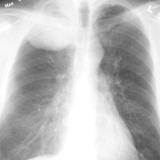

SCLC

Album: SCLC

Date: 10/01/2006

Size: 3 items

Views: 30062